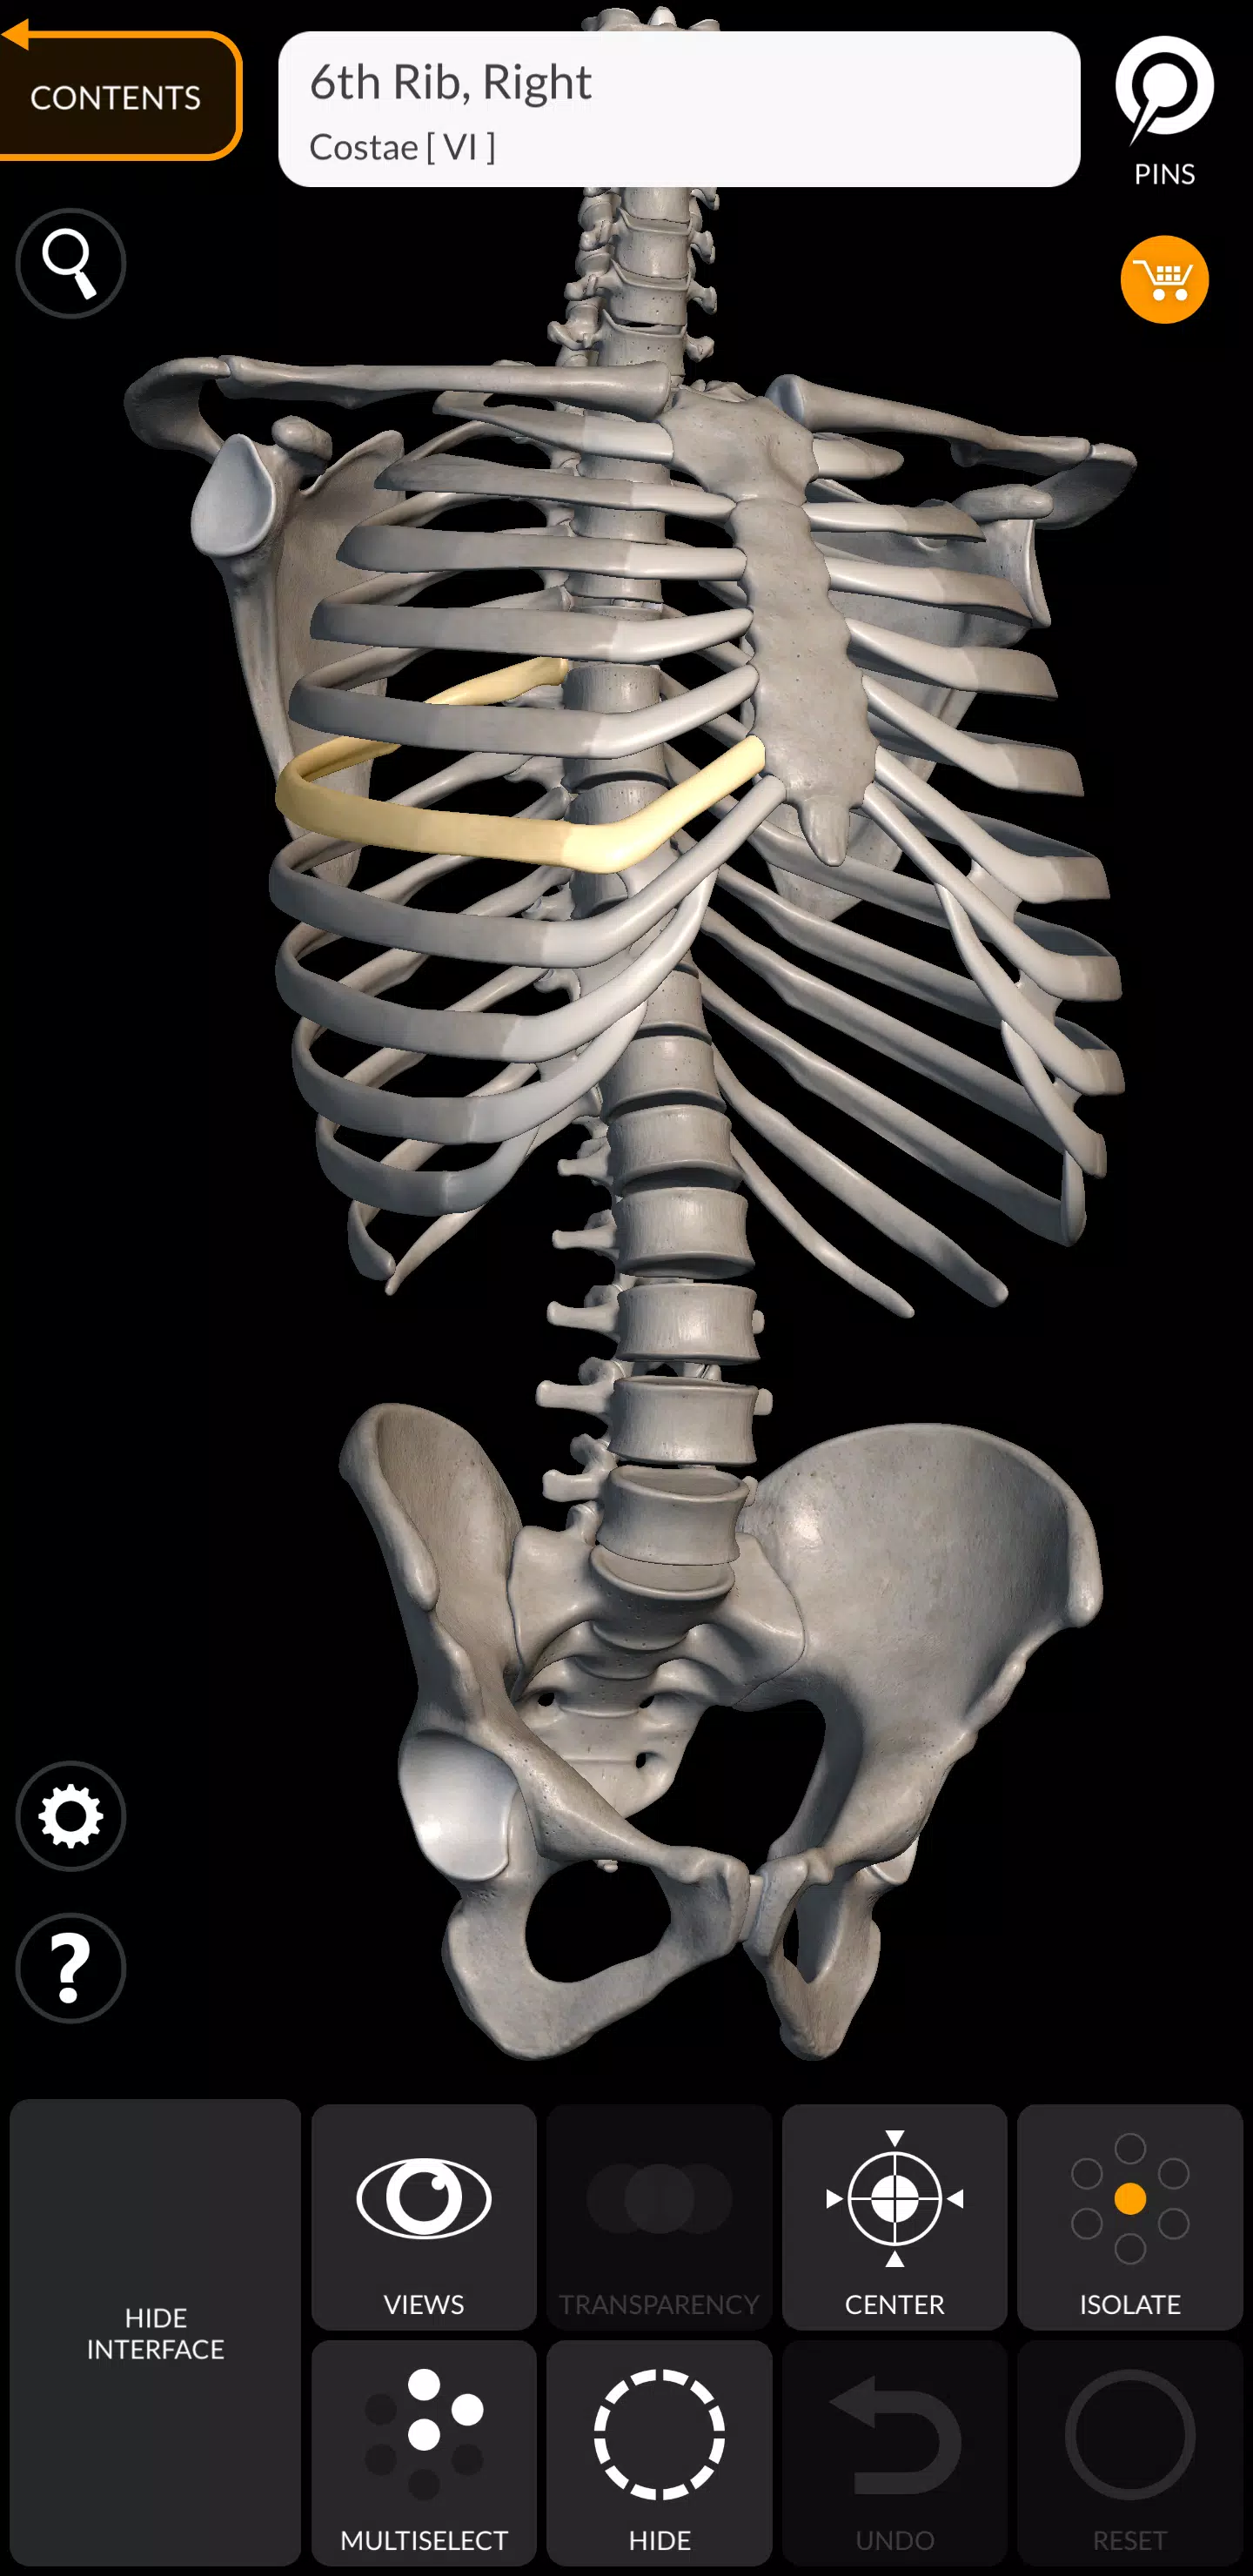

„Szkielet | Atlas 3D anatomii” to najnowocześniejszy atlas anatomii 3D, który zapewnia niezrównane interaktywne doświadczenie z bardzo szczegółowymi modelami anatomicznymi. To narzędzie nowej generacji rewolucjonizuje sposób, w jaki eksplorujesz ludzki szkielet, oferując dogłębną, trójwymiarową perspektywę, która poprawia twoje zrozumienie anatomii szkieletowej.

Każda kość w ludzkim szkielecie została skrupulatnie zrekonstruowana w 3D, co pozwala obracać i powiększać każdy model, aby obserwować skomplikowane szczegóły pod dowolnym kątem. Ten poziom szczegółowości jest idealny zarówno do użytku edukacyjnego, jak i profesjonalnego, oferując kompleksowy obraz struktury szkieletowej.

Bardzo szczegółowe anatomiczne modele 3D

- Układ szkieletowy: kompleksowe pokrycie całego układu szkieletowego.

- Dokładne modelowanie 3D: precyzyjne rekonstrukcje do dokładnego uczenia się.

- Tekstury o wysokiej rozdzielczości: powierzchnie szkieletu z teksturami do rozdzielczości 4K w celu uzyskania szczegółowej wizualizacji.